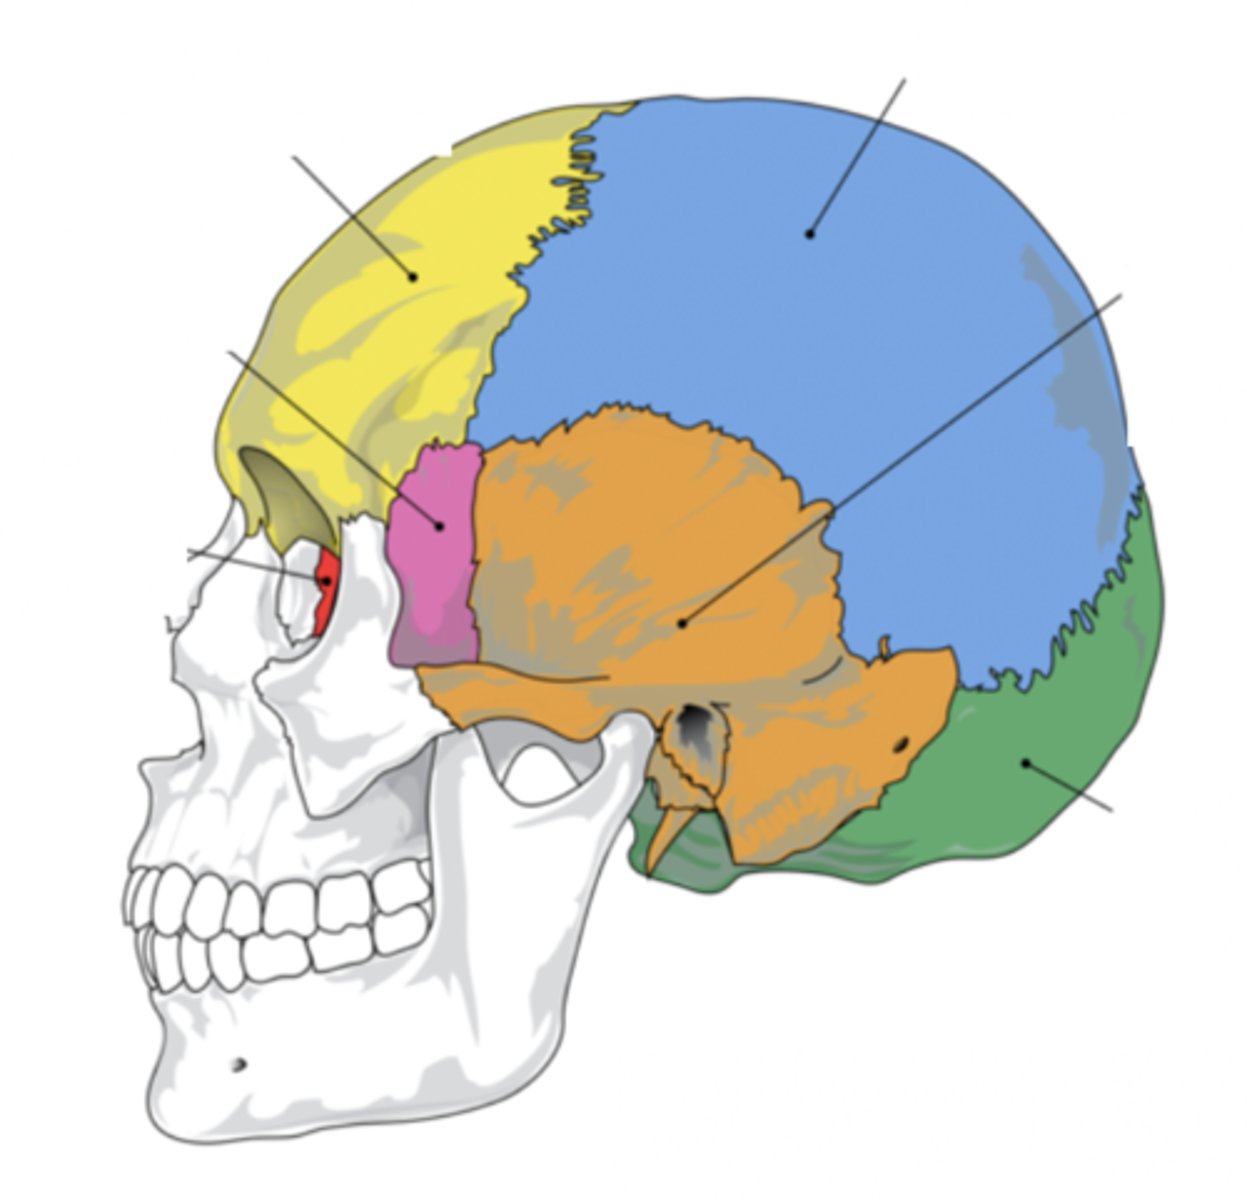

Cranial Bones (8)

- Ethmoid

- Frontal

- Sphenoid

- Temporal (2)

- Occipital

- Parietal (2)

(EFSTOP)

Ethmoid Bone

Forms part of the posterior portion of the nose, the orbit, and the floor of the cranium (red)

Frontal Bone

Bone that forms the forehead (yellow)

Sphenoid Bone

Forms part of the base of the skull and parts of the floor and sides of the orbit (pink)

Temporal Bone (2)

Bone that forms parts of the side of the skull and floor of the cranial activity (orange)

Occipital Bone

Bone that forms the back of the head (green)

Parietal Bone (2)

Either of two skull bones between the frontal and occipital bones and forming the top and sides of the cranium (blue)